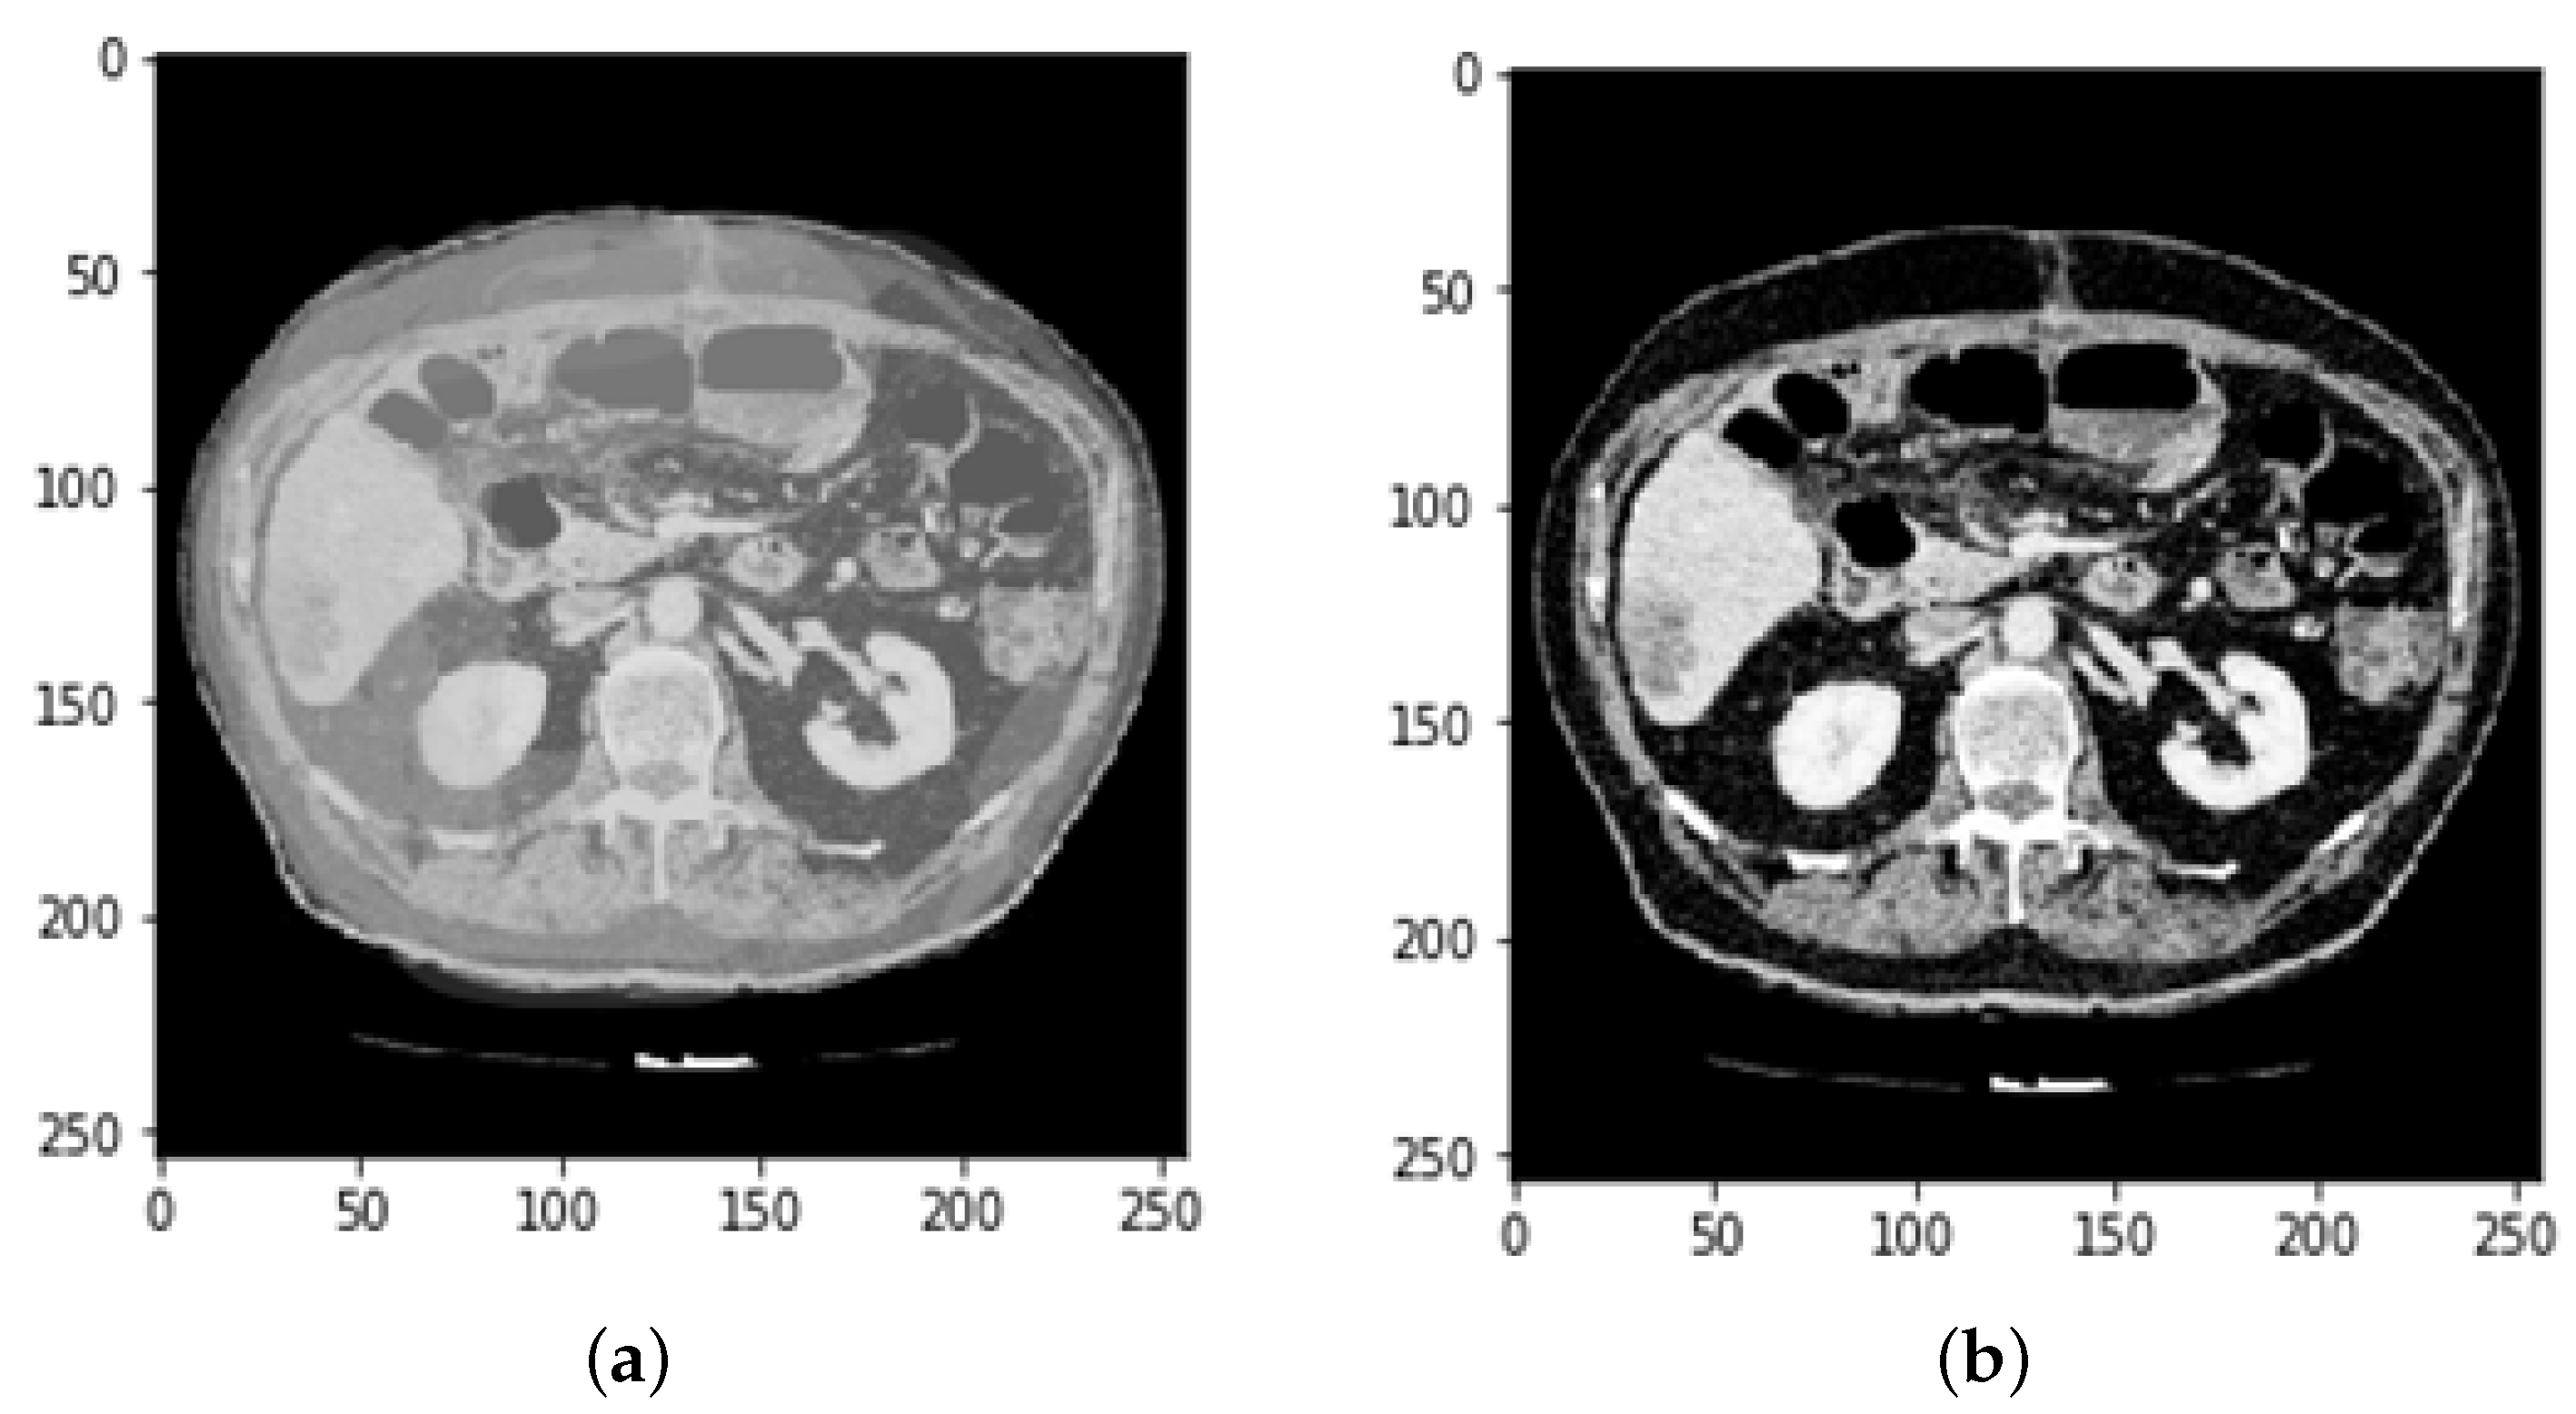

3.2. CT and MRI Images Preprocessing

3.4. Defining Region of Interest (ROI)